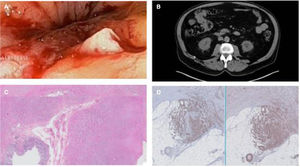

Se realizó una colonoscopia, en la que se detectó una estenosis infranqueable en el colon transverso, con bordes de aspecto adenomatoso y ulceración, con friabilidad y sangrado espontáneo al roce del endoscopio (fig. 1A), de la cual se tomaron múltiples biopsias, siendo negativas para malignidad, dado el origen subepitelial de esta lesión. Asimismo, se realizó tatuaje con tinta china para su localización posterior. En la TC (fig. 1B) se visualizó una masa en el colon transverso, de carácter estenosante, sin evidencias de lesiones metastásicas.

A)Imagen endoscópica de una estenosis infranqueable, con bordes de aspecto adenomatoso y friabilidad al roce, y su correlación radiológica en un corte de TC (B) en el que se aprecia una masa en colon transverso que estenosa la luz intestinal sin dilatación retrógrada. C,D)En la anatomía patológica se confirma la presencia de un leiomiosarcoma colónico positivo a actina y desmina, con negatividad para marcadores de GIST como CD117.

El paciente fue derivado a cirugía, y finalmente fue intervenido. El estudio anatomopatológico de la pieza resecada objetivó células tumorales compatibles con un tumor mesenquimal, que en el estudio inmunohistoquímico presentaba positividad para actina y desmina, confirmando el diagnóstico de leiomiosarcoma (fig. 1C,D).